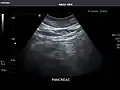

Right kidney